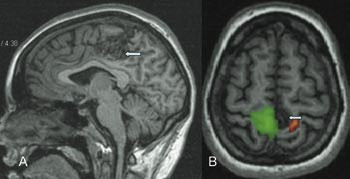

Ved å stimulere ulike hjerneavsnitt med forskjellige triggere kan elokvente områder lokaliseres med bakgrunn i endret oksygenforbruk i det aktuelle hjerneavsnittet. Lysstimuli kan brukes for å lokalisere synsbarken, motorisk stimulering, som finger- eller tåbevegelse, for å fremstille motorisk cortex (fig 1), og man kan med språkvariabler kartlegge Brocas og Wernickes område. Dette er viktig der en sykelig prosess ligger nær disse elokvente strukturene, slik at operasjonen kan planlegges for å unngå skade.